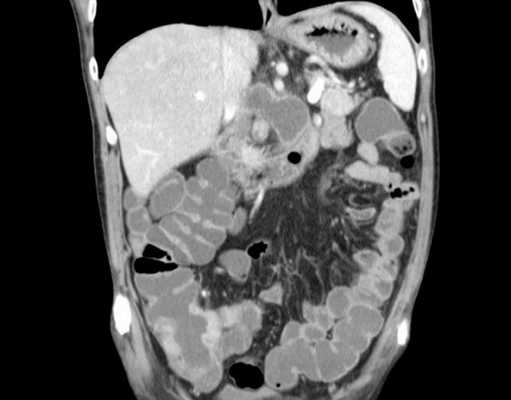

г) Типичные находки:

• Рак: видимая опухоль (первичная опухоль толстой кишки не всегда визуализируется на КТ), признаки метастазирования, инвазия или опасная близость к другим структурам и т.д.

• Перитонит/внутрибрюшная катастрофа: формирование абсцесса (тазового, периколического, подпеченочного, поддиафрагмального, межкишечного и т.д.), признаки выхода контраста (несостоятельность, перфорация), воздух вне просвета?

• Дивертикулит (важен для стадирования/возможного вмешательства): флегмона, утолщение стенки кишки, тяжистость жировой клетчатки, формирование абсцесса (периколического, тазового), осумкованный газ вне кишки, свободный газ, асцит.

а - Маленький околотолстокишечный абсцесс при дивертикулите. Фокус скопления воздуха наблюдается вне контура просвета кишки (показано длинной стрелкой) в центре мягкотканного тяжа жировой ткани, идущего к сигмовидной кишке.

В брыжейке сигмовидной кишки видна жидкость (короткая стрелка). Компьютерная томография.

б - Большой околотолстокишечный абсцесс при дивертикулите. Полость абсцесса содержит воздух и остатки тканей (показано стрелкой), толстая стенка абсцесса усиливает контрастность.

Компьютерная томография.